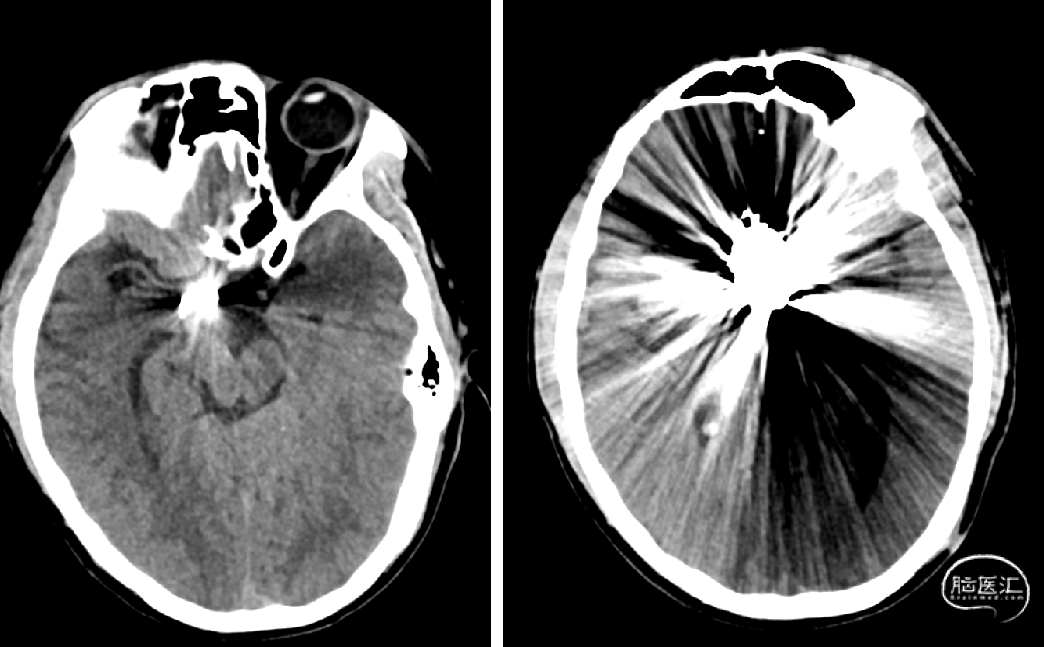

术前检查

术后CT未见出血及梗塞